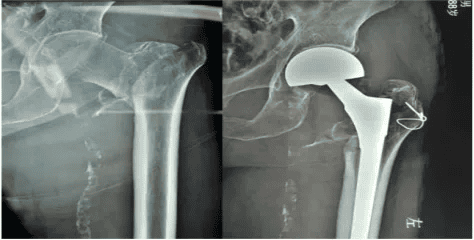

2.1 股骨转子间骨折内固定手术:

股骨转子间骨折的手术治疗方法首选内固定手术,目前临床上常用的手术方式包括PFNA、DHS等闭合复位内固定术及股骨近端钢板固定等切开复位内固定术。PFNA适用于大多数老年髋部骨折患者,并可做到微创解决骨折问题,其具有创伤较小、可早期康复训练、并发症少等优势。

2.2 髋关节置换术:

适用于患侧髋关节既往存有症状的病变,骨折合并骨肿瘤、股骨头坏死、严重骨质疏松、内固定难以进行有效固定,内固定失败需要翻修。